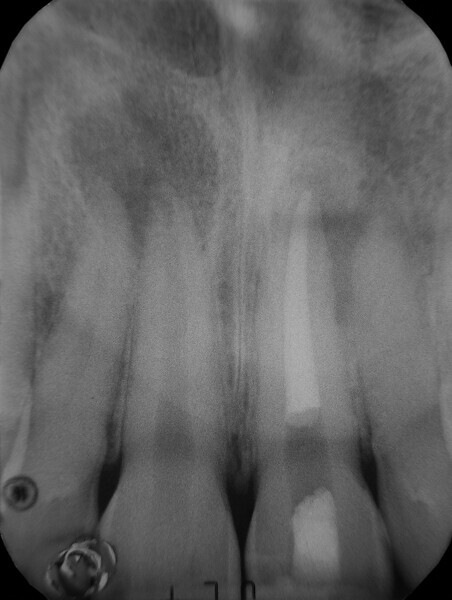

Irrigating the root canal: A case report